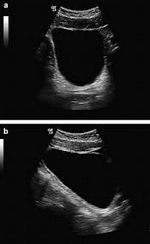

Urinary catheterization is the insertion of a catheter into a patient's bladder. The catheter is used as a conduit to drain urine from the bladder into an attached bag or container